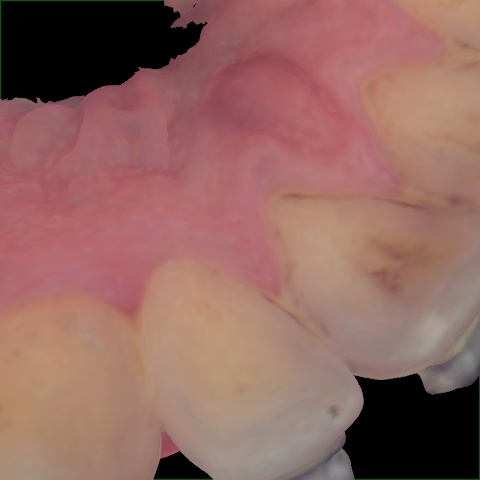

Annotated as "Good"